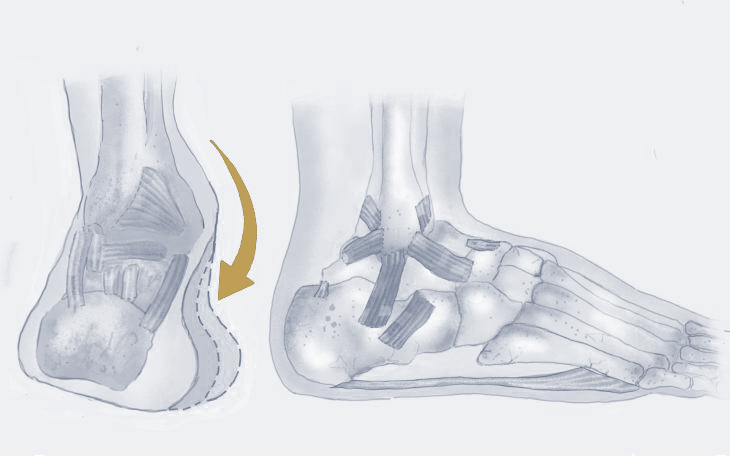

Wann wird Taping oder Verbände empfohlen?

Taping und Verbände werden vor allem bei akuten oder wiederkehrenden Verletzungen im Bereich des Sprunggelenks und Fußes eingesetzt. Typische Indikationen sind Bänderdehnungen oder -risse, leichte bis mittlere Instabilitäten, Überlastungssyndrome von Sehnen, Prellungen oder zur Korrektur von Fehlstellungen. Auch zur Prophylaxe, beispielsweise bei sportlicher Belastung oder nach überstandener Verletzung, kann Taping sinnvoll sein. Darüber hinaus kann Taping nach minimalinvasiven Eingriffen angewendet werden, um ein optimales postoperatives Ergebnis zu erzielen.

Ablauf der Therapie

Beim Taping und Anlegen von Verbänden im Fuß- und Sprunggelenksbereich erfolgt zunächst eine Untersuchung von Fußstellung, Stabilität und Schmerzzonen. Danach wird die Haut vorbereitet und das Tape oder der Verband so angelegt, dass er gezielt Stabilität gibt, Überbewegungen verhindert und die natürliche Fußfunktion unterstützt. Je nach Verletzung oder Fehlstellung kommen funktionelle Tapes (z. B. bei Bänderdehnung am Sprunggelenk), Kinesiotapes zur Muskelunterstützung oder stabilisierende Verbände bei akuten Verletzungen zum Einsatz.

Vorteile der Therapie

• Stabilisierung von Sprunggelenk und Fußgewölbe ohne komplette Ruhigstellung

• Schmerzlinderung bei akuten Verletzungen wie Distorsionen

• Unterstützung der Heilung von Bänder- und Sehnenverletzungen

• Verbesserung der Propriozeption und Gelenkführung

• Individuelle Anpassung an Fußform und Belastungsniveau

Nach der Therapie

Das Tape oder der Verband sollte regelmäßig kontrolliert und bei Bedarf erneuert werden, um Halt und Hautverträglichkeit sicherzustellen. Nach der Abnahme ist es wichtig, die Beweglichkeit des Sprunggelenks schrittweise wiederherzustellen und die Fußmuskulatur durch gezielte Übungen zu kräftigen. So wird einem erneuten Umknicken oder einer Fehlbelastung vorgebeugt.